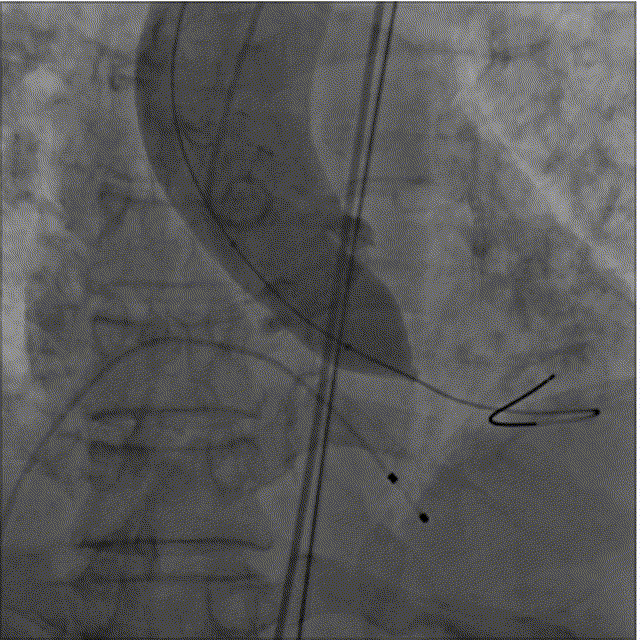

SinoCrown瓣膜逐步释放

SinoCrown瓣膜释放后已工作(解锁前)

SinoCrown瓣膜完全释放后最终造影(解锁后)